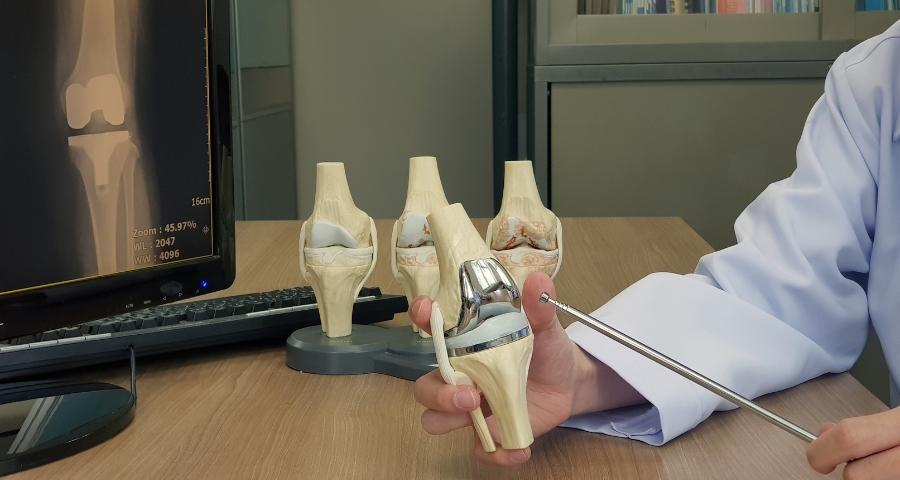

Chẩn đoán bệnh thoái hóa khớp háng

Để chẩn đoán được chính xác về bệnh thoái hóa khớp háng, bác sĩ sẽ kết hợp kiểm tra về các triệu chứng và tiền sử bệnh cùng với các xét nghiệm chẩn đoán, chẳng hạn như chụp X-quang.

Kiểm tra hình ảnh

Chụp X-quang khớp háng có thể cho thấy không gian khớp bị thu hẹp, các thay đổi trong xương và sự hình thành các gai xương (các tế bào xương).

Điều trị phẫu thuật

Bác sĩ có thể đề nghị phẫu thuật nếu người bệnh sử dụng phương pháp điều trị không phẫu thuật không thuyên giảm và có nguy cơ tàn tật.

Thay thế hông

Bác sĩ sẽ loại bỏ cả miếng đệm và chỏm xương đùi bị hỏng, sau đó định vị các bề mặt khớp bằng kim loại, nhựa hoặc gốm mới để phục hồi chức năng của khớp háng.

Tái tạo bề mặt hông

Trong quy trình thay khớp háng này, xương và sụn bị hư hỏng trong khớp nối (ổ khớp háng) được loại bỏ và thay thế bằng một lớp vỏ kim loại. Tuy nhiên, phần đầu của xương đùi không bị loại bỏ mà thay vào đó được bọc bằng một lớp kim loại mịn.